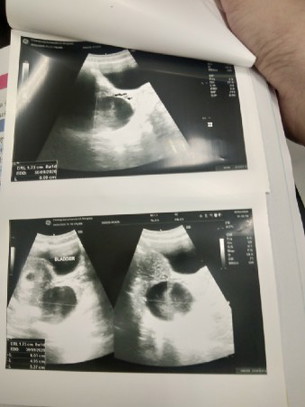

ท้องได้ 8 สัปดาห์ 2 วัน แต่มีถุงน้ำด้านซ้าย 6 เซนติเมตร

วันนี้ไปหาหมอไปซาวดูเด็ก แต่พบถุงน้ำนอกมดลูก 6 เซนติเมตร ไม่รู้ว่าต้องรักษายังไง ทำตัวแบบไหนบ้างหมอบอกแค่ว่านัดตรวจอีกที ถ้าปวดมาก ต้องผ่าตัดอาจเสียเด็กไป ซึ่งมันน่าเศร้าใจมาก เครียดมาก เพราะเราตัดปีกข้างขวาไปแล้ว ตัดอีกเราก็ไม่สามารถมีได้อีกเลย ใครมีคำแนะนำอะไรบอกได้นะคะ ช็อคมากคะ

อ่านเพิ่มเติมไม่ต้องตกใจนะคะแม่ ของเราก็มีค่ะ เห็นก้อนดำๆฝั่งขวามั้ยคะ ซีสถุงน้ำเหมือนกันค่ะ ใหญ่ๆกว่าลูกอีก 🤣🤣 แต่หมอเราก็แจ้งเหมือนของคุณแม่เลยค่ะ 50 50 อาจเสียลูก อาจหาย เหมือนหมอให้เราระวังมากขึ้น แต่เราไม่เครียดเลยค่ะแม่ ยิ่งเครียดยิ่งส่งผลต่อลูก เราต้องเข้มแข็ง คิดบวกตลอดว่าลูกเราต้องรอด ต้องสู้ไปด้วยกัน ตอนนี้14วีคแล้ว ซีสเล็กลงไม่ต้องผ่าละค่ะมันจะฝ่อไปเอง สู้ๆค่ะแม่

คุณแม่มีทั้งถุงตั้งครรภ์ในมดลูก แล้วก็ถุงน้ำที่ปีกมดลูก 6 ซม ใช่มั้ยคะ ถ้าเป็นอย่างนั้นก็อย่าเพิ่งกังวลไปค่ะ ถุงน้ำมีโอกาสเล็กลงได้อยู่ ช่วงนี้ก็คอยสังเกตุอาการปวดท้องตามที่หมอบอก ถ้าท้องเลย 3 เดือนไปความเสี่ยงที่จะต้องผ่าก็น่าจะลดลงค่ะ